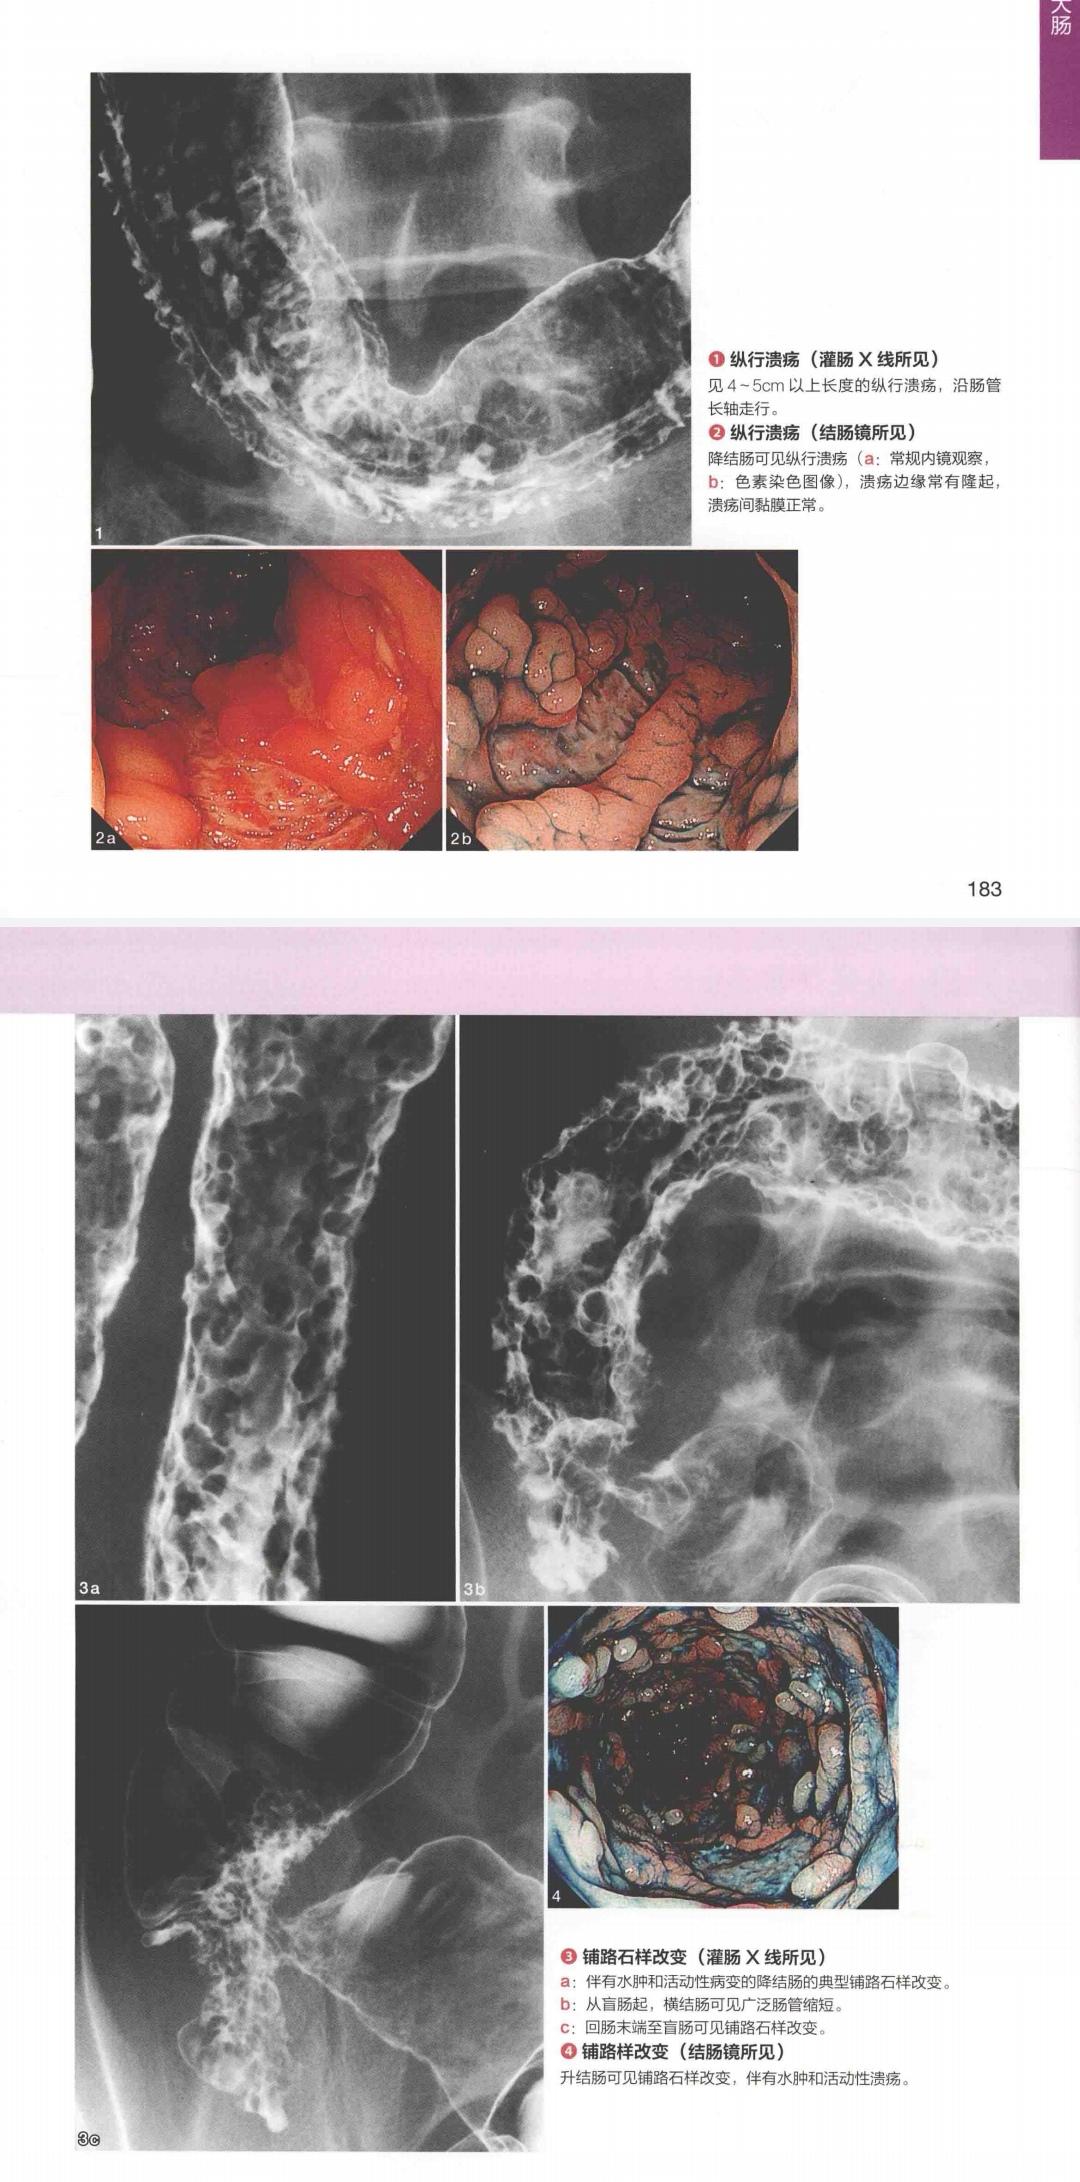

【资料】典型的克罗恩病的肠镜图片 [精华]